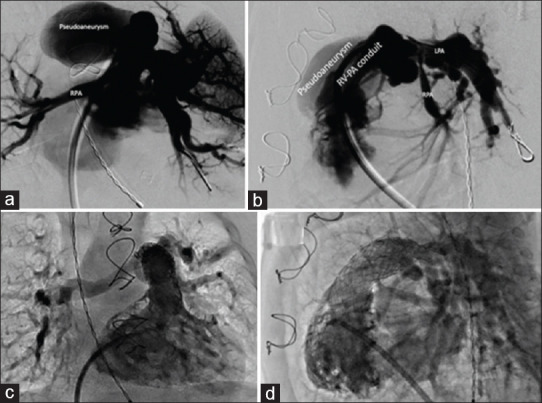

Pseudoaneurysm formation within the right ventricular outflow tract (RVOT) is a rare but serious complication following cardiac surgeries involving the RVOT. This report presents the case of a 3-month-old, 4 kg infant with tetralogy of Fallot and pulmonary atresia, previously treated with ventricular septal defect closure and right ventricle (RV)-pulmonary artery homograft placement. The patient presented critically ill with septic shock and suprasystemic RV pressure. A high-risk surgical approach was averted through the endovascular exclusion of the pseudoaneurysm using a Gore VBX® balloon expandable covered stent, in addition to stenting of bilateral proximal branch pulmonary arteries to alleviate RV hypertension. This case underscores the multifactorial nature of RVOT pseudoaneurysm formation and the importance of a high index of suspicion for diagnosis. Management options, including surgical and transcatheter strategies, are discussed, focusing on the successful use of a covered stent for stabilization in a critically ill patient.